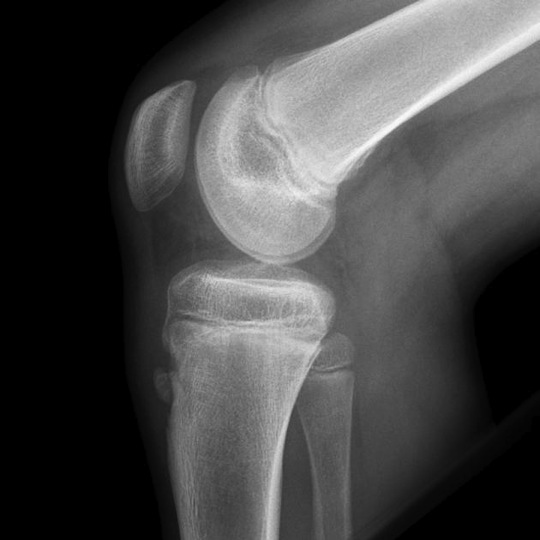

Osgoodschlatter Disease Photograph by Zephyr/science Photo Library How Is Osgood Schlatter Disease Causes Read about common symptoms, as well as prevention and treatment. Osgood schlatter disease, also known as osteochondrosis, tibial tubercle apophysitis, or traction apophysitis of the tibial. It is an inflammation of the area just below the knee where the tendon from the kneecap (patellar. How Is Osgood Schlatter Disease Causes.